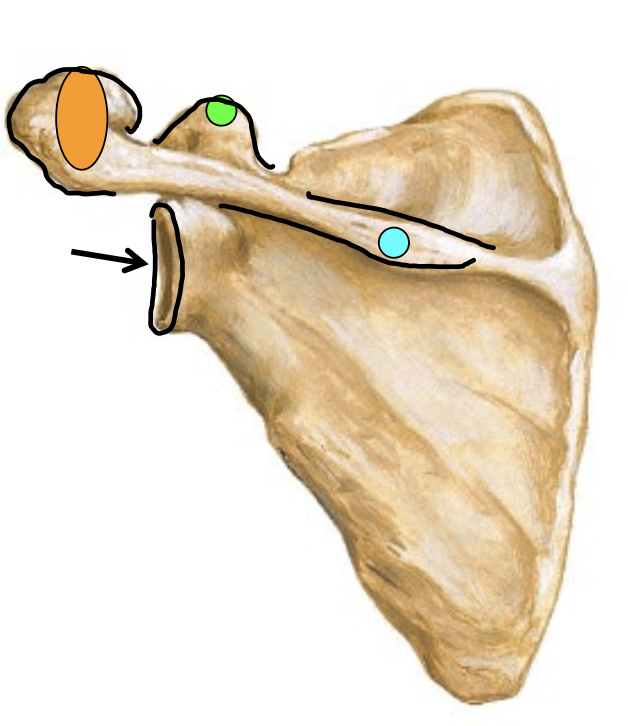

What is the arrow locating in this image?

Glenoid Fossa

What is the blue dot locating in this image?

Spine of scapula

What is the orange dot locating in this image?

Acromion process

What is the green dot locating in this image?

Caracoid process